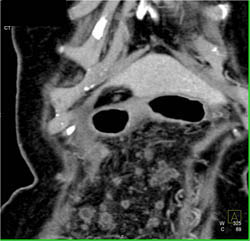

Islet Cell Tumor With Liver Matastases